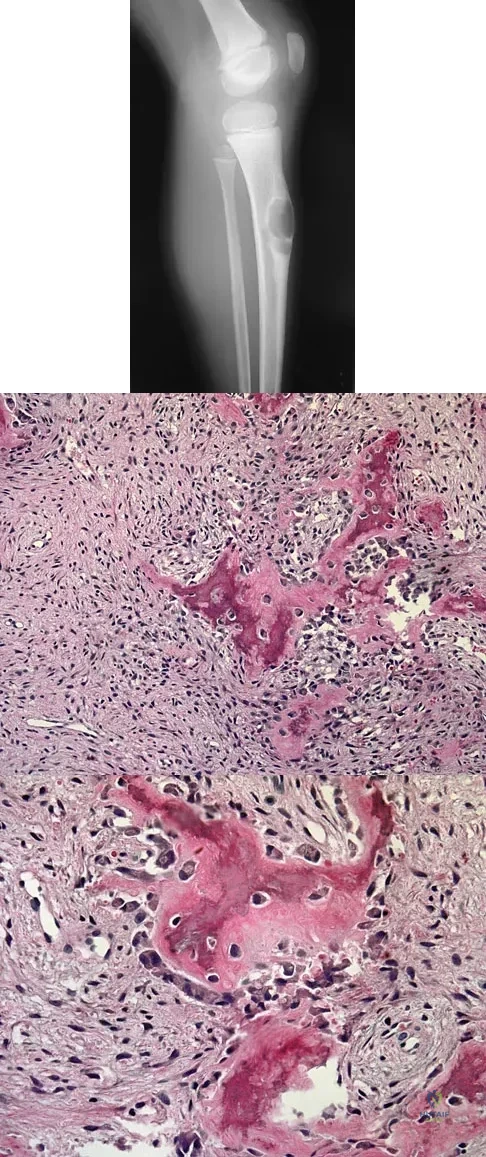

Figures 12a through 12e show the radiograph, MRI scans, and biopsy specimens of a 17-year-old boy. What is the most likely diagnosis?

Explanation